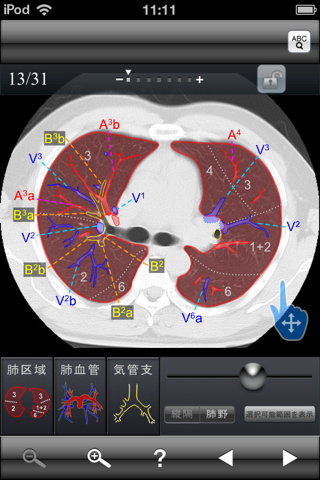

・肺区域、血管、気管支を表示できます。

撮影画像:肺野条件、縦隔条件

スライス数: 31(各条件)

解剖名数: 15(肺野条件)、66(縦隔条件)